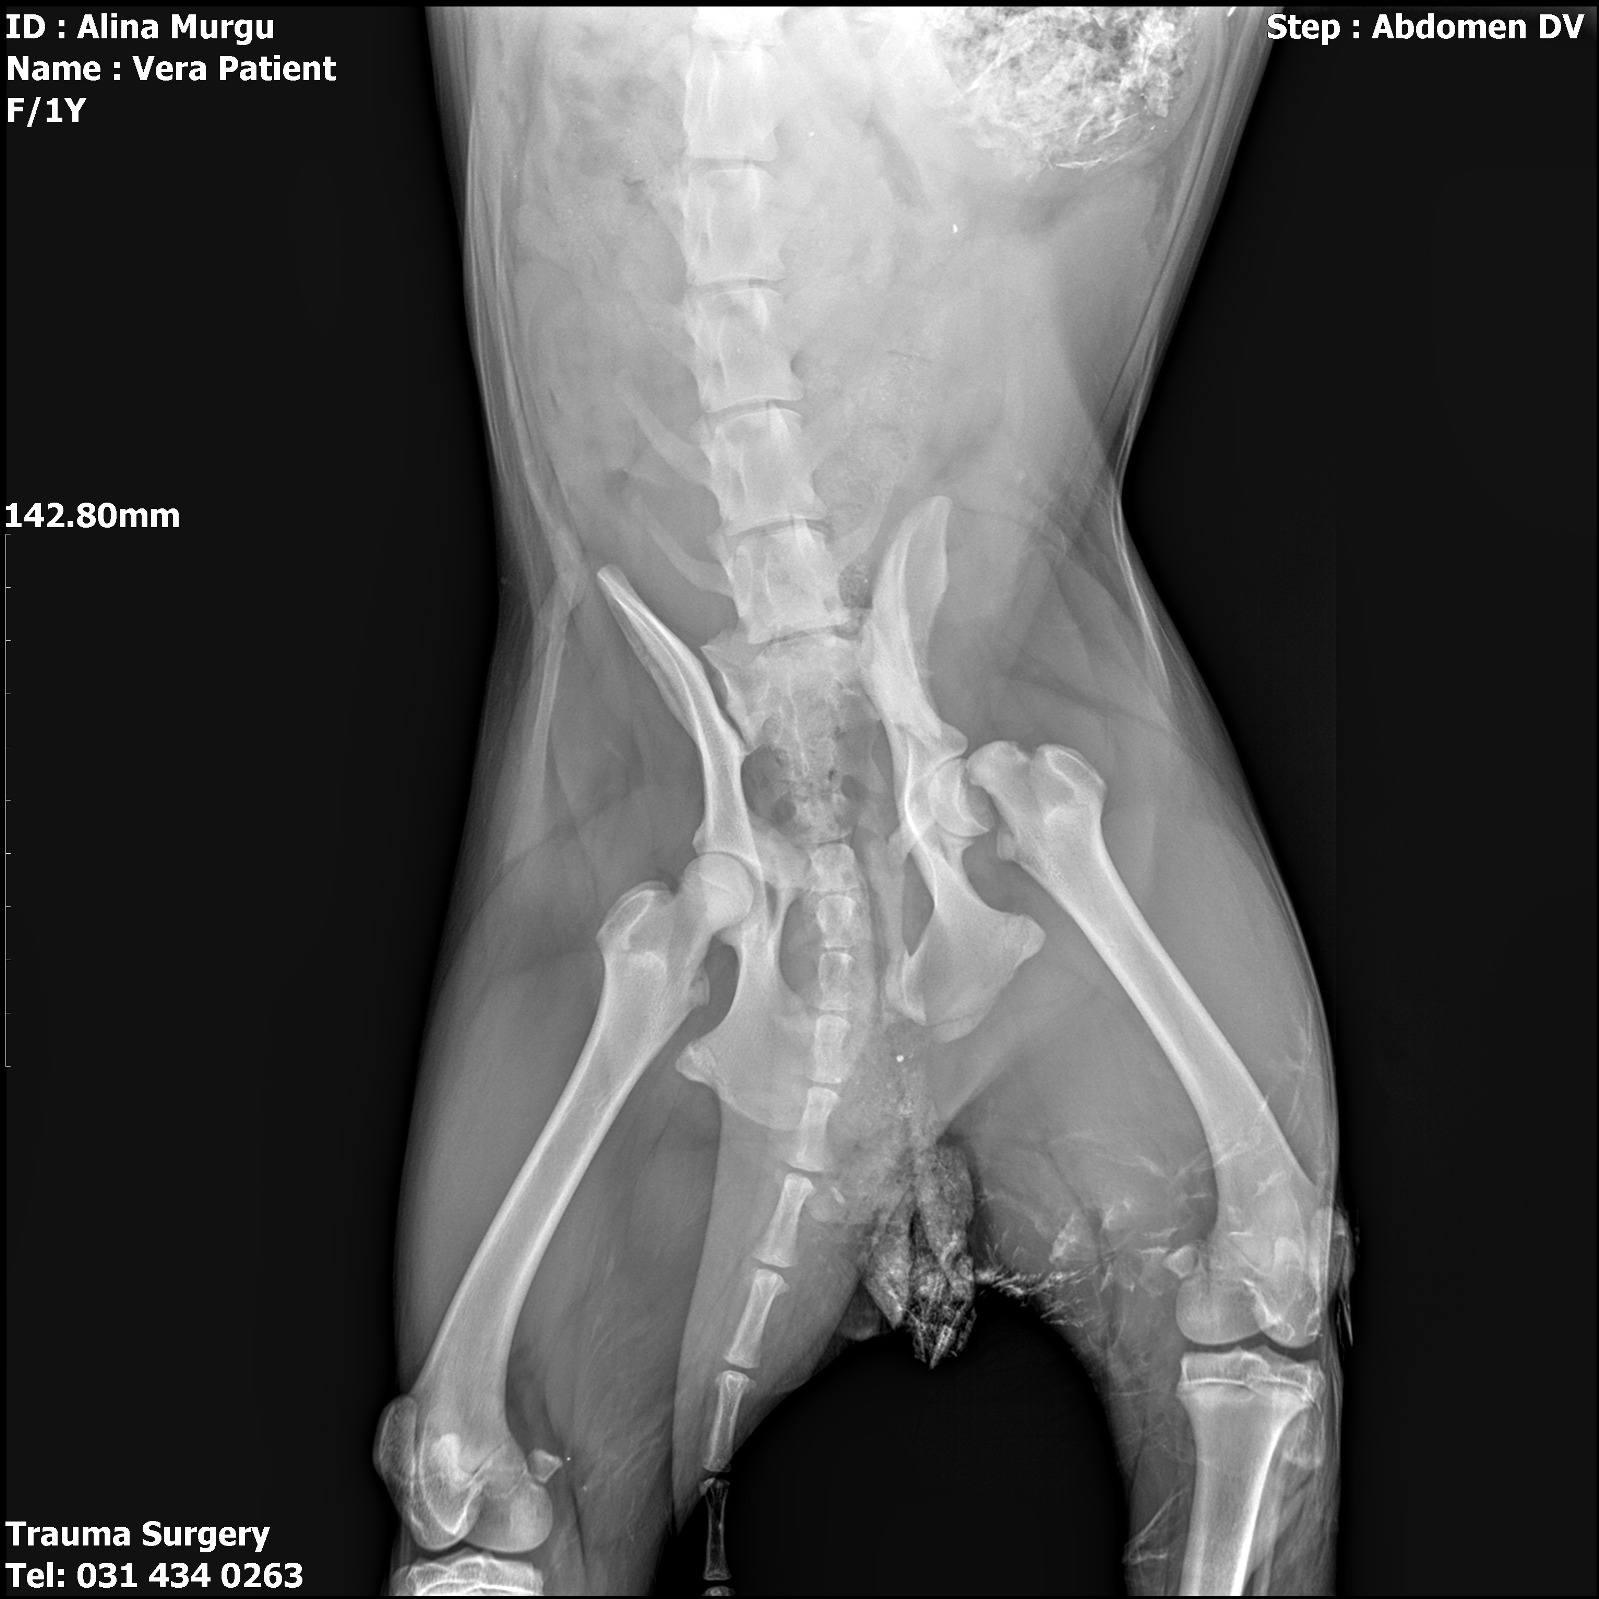

Le diagnostic est lourd : cette chienne courageuse souffre d’une fracture du bassin et a quatre côtes cassées. Face à ces blessures qui menacent sa vie et sa mobilité, le verdict des vétérinaires est sans appel : une intervention chirurgicale est nécessaire, et elle a eu lieu le jour même.